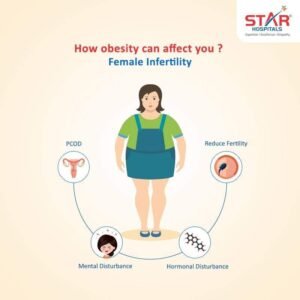

إن البدانة شائعة بين النساء بسن الإنجاب و لديها دور في الاضطرابات الإنجابية لديهن وانخفاض الخصوبة وذلك بسبب الأمراض الناتجة عن السمنة كالسكري وتوقف التنفس أثناء النوم وأيضا ما تسببه من مشاكل واضطرابات هرمونية.

- كما تؤهب لحدوث متلازمة تكيس المبايض والتي تعد أشيع أسباب العقم

وهناك ارتباط وثيق بين السمنة ومتلازمة تكيس المبايض pco ومن المظاهر المميزة للمتلازمة النمو المفرط للشعر، زيادة الوزن، واضطرابات الدورة الشهرية.